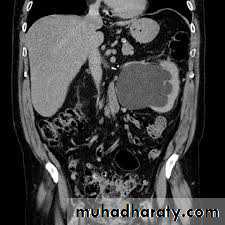

US: pre- and post-natal.IV Urography

Isotope renal scan.

CT & MRI